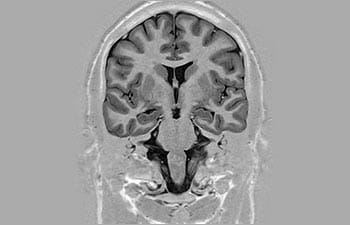

Mayor fiabilidad diagnóstica en neurooncología